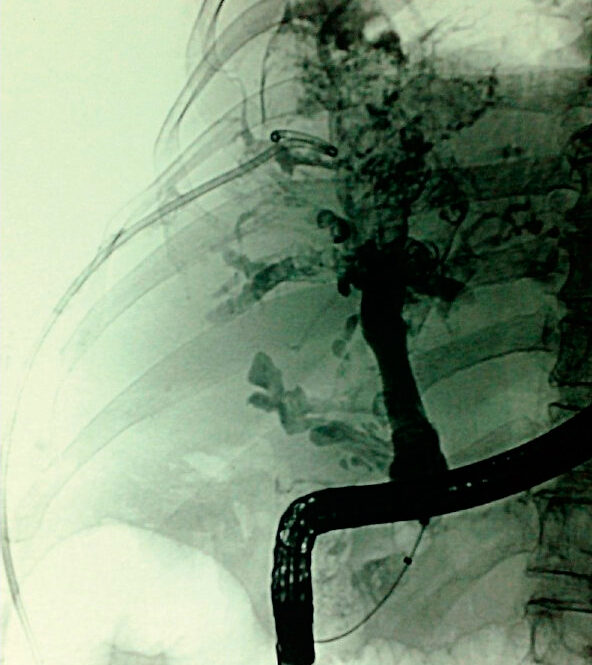

Η αρτηριογραφία αποτελεί αυτή τη στιγμή την εξέταση εκλογής επί υποψίας αιμοχολίας και θα αποκαλύψει την πηγή της αιμοχολίας στο 90% των περιπτώσεων. Η χολαγγειογραφία αναδεικνύει θρόμβους στο χοληφόρο δένδρο, οι οποίοι μπορούν να παρουσιάζονται σαν γραμμοειδείς ή σφαιρικές αλλοιώσεις, οι οποίες μπορούν δύσκολα να διαχωρισθούν από λίθους.

Η θεραπεία της αιμοχολίας πρέπει να εστιασθεί στον έλεγχο και στη διακοπή της αιμορραγίας, καθώς και στην αντιμετώπιση της απόφραξης των χοληφόρων. Πολλές περιπτώσεις ελαφράς αιμοχολίας μπορεί να αντιμετωπισθούν συντηρητικά με διόρθωση των διαταραχών της πήξης, επαρκή παροχέτευση της χολής και στενή παρακολούθηση του ασθενούς. Σε μια μελέτη 171 περιστατικών από το 1996 έως το 1999, 43% των ασθενών αντιμετωπίσθηκαν συντηρητικά. Η πρώτη γραμμή θεραπείας σε ασθενή με σοβαρή αιμοχολία είναι ο ενδαρτηριακός εμβολισμός, με αναφερόμενα ποσοστά επιτυχίας 80-100%. Η αρτηριογραφία σε συνδυασμό με ενδαρτηριακό εμβολισμό ενδείκνυται για σοβαρή αιμοχολία όπου απαιτείται μετάγγιση αίματος (εικόνα 2).